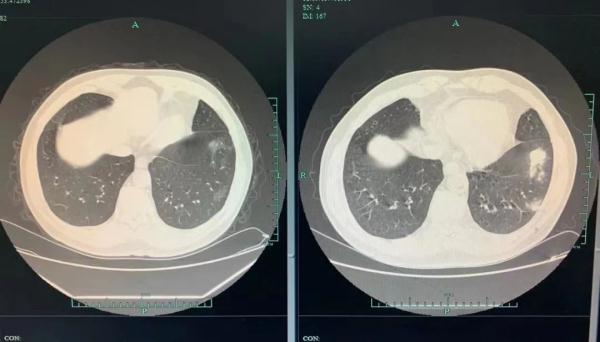

老大爷肺部CT显示“多发肺结节”

杭州70岁的张大爷(化名)在一次体检中,肺部CT结果显示“多发肺结节”,几个团状阴影被医生指了出来。突如其来的结果把张大爷吓得不轻,赶紧来到医院。

3个月前、后

还好发现及时,只是轻度炎症,张大爷回家以后按照医嘱服用抗真菌药物,忍住不去西湖喂鸽子。经过3个月的治疗,张大爷再回到金医生门诊复查时,肺结节明显变小了,一家人这才松了口气。